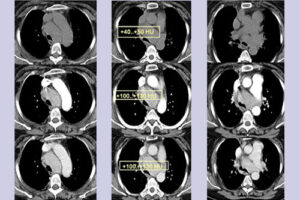

- Компьютерная томография (КТ) с внутривенным введением контрастного вещества

- Игольчатая биопсия или аспирационная биопсия или пункционная биопсия под контролем КТ